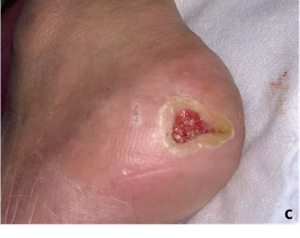

糖尿病、慢性腎不全で長期透析歴のある患者。介入1ヶ月前より左踵の褥瘡に痛みの強い潰瘍が出現し、通院加療を行なっていたが改善せず紹介となっている(図7a)。

Wound Hygieneのコンセプトに従い、毎日の石鹸を用いた洗浄処置を指示し、適宜メンテナンスデブリードマンを試行。バイオフィルム対策としてアクアセル®Agアドバンテージを被覆材として使用した(図7b)。治療開始1ヶ月後の診察では一気に創部が縮小し、肉芽表面の色調も良好であることがわかる(図7c)。治療開始2ヶ月後、順調に上皮化が進んでおり、痛みも改善している(図7d)。治療開始3ヶ月後、上皮化が進行し治癒していることがわかる(図7e)。従来の治療法に比べ治癒期間がかなり短縮できた印象であった。

図7 60代/男性/左踵部潰瘍

a: 治療開始時の所見 痛みの強い潰瘍

Wound Hygieneに従い治療開始

b: 銀含有創傷被覆材を使用して治療

c: 治療開始1ヶ月 創部縮小。肉芽の状態良好

d: 治療開始2ヶ月 順調に上皮化が進行

e: 治療開始3ヶ月 治癒した。